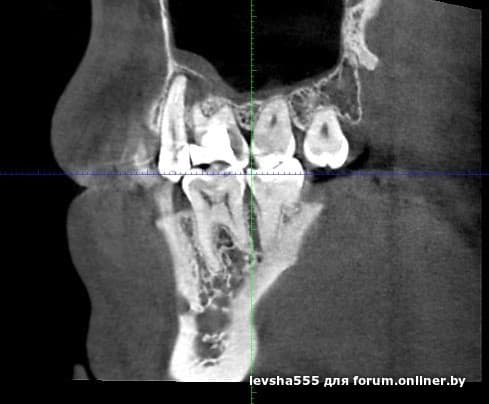

Добрый день форумчане стоматологи. Может кто-нибудь подскажет по данной проблеме. Этим летом в июле удалил 6 зуб справа сверху (вылез свищ перед этим). Далее через неделю после удаления свищ закрылся. И вот в ноябре, на месте удаленного 6 зуба в десне на внешней части снова вылез свищ. Сделал КЛКТ но к хирургу с этим диском еще не попал. Подскажите в чем может быть проблема , почему свищ снова появился ? прилагаю скриншоты c КТ за месяц до удаления зуба и с КТ сделанного вчера.

levsha555:Добрый день форумчане стоматологи. Может кто-нибудь подскажет по данной проблеме. Этим летом в июле удалил 6 зуб справа сверху (вылез свищ перед этим). Далее через неделю после удаления свищ закрылся. И вот в ноябре, на месте удаленного 6 зуба в десне на внешней части снова вылез свищ. Сделал КЛКТ но к хирургу с этим диском еще не попал. Подскажите в чем может быть проблема , почему свищ снова появился ? прилагаю скриншоты c КТ за месяц до удаления зуба и с КТ сделанного вчера.